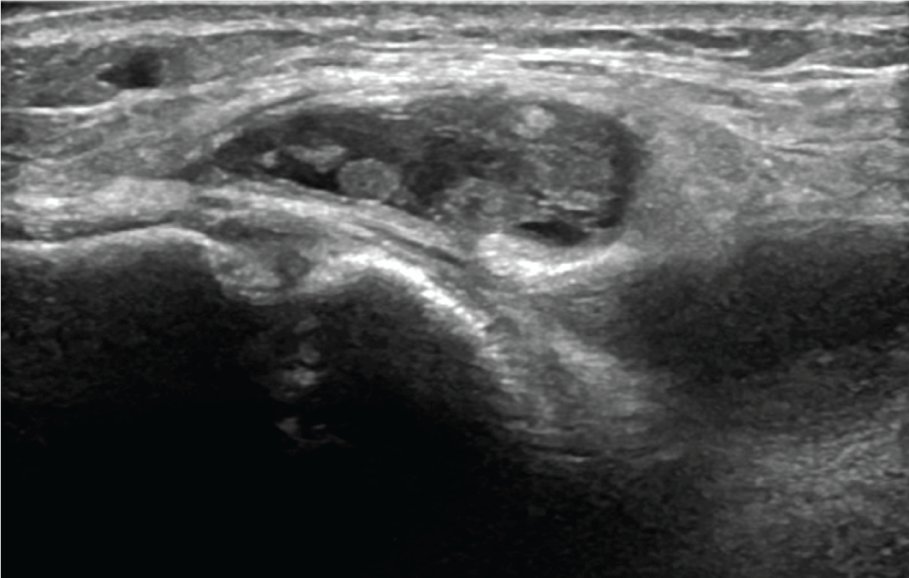

Thirteen year old boy with no medical history consulted our medical department for the spontaneous appearance of a progressively growing though painless mass on the medial aspect of his right knee. Intake excluded any kind of clinical or functional symptomatology or preceding traumatic events. Physical examination revealed a soft, painless, mobile, mass on the medial side of the knee joint. Strength and range of motion were preserved, painless medial joint interline palpation and negative medial meniscus manoeuvres. The ultrasound exam documented a cystic mass, apparently emerging from the bursa anserine (Figure 5). Additionally, 13 cubic centimetres of blood-synovial fluid were obtained when a puncture was performed. MRI demonstrated a bilobed collection that was located between the tendons of the pes anserinus and the tibial plateau (Figure 6 and Figure 7). As a focal extra-articular PVNS was suspected, the patient was referred to a hospital where an open bursectomy and pathological examination were performed. The result of microscopic and macroscopic exams confirmed the diagnosis of PVNS. No postoperative complications were reported and the patient remained asymptomatic.

Figure 5: Ultrasound exam of the medial side of the knee shows a cystic image with echoes inside emerging extra-articular from the bursa anserine.